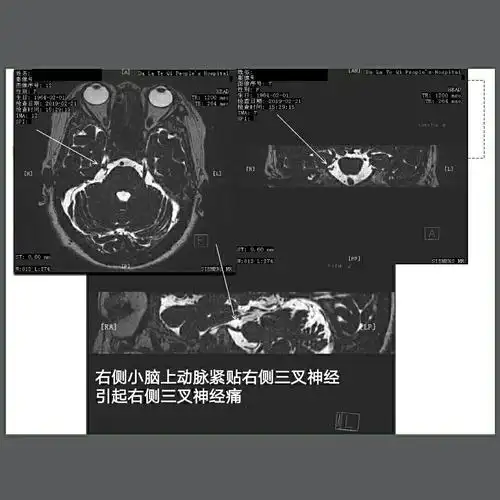

三叉神经(痛),面神经面肌痉挛血管磁共振成像mrta技术 - 好大夫在线

其它 学以致用,方便他人,快乐自己! 写美篇三叉神经痛的病因在哪里?

根治三叉神经痛,从致病血管做起_三叉神经痛_三叉神经痛治疗方式 - 好

了头颅ct与磁共振扫描检查,发现她颅内胆脂瘤体积巨大,包绕了三叉神经